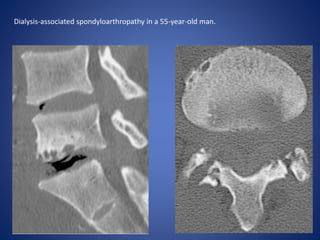

Characteristics of dialysis-associated spondyloarthropathy include

intervertebral disk space loss, extensive vertebral endplate

erosion and cyst formation, and minimal formation of endplate

spurs.

Dialysis-associated spondyloarthropathy in a 55-year-old man.

T1W FATSAT T2W FATSAT

• #32 Sagittal CT image of the lumbar spine demonstrates L5-S1 intervertebral space narrowing; a disk vacuum phenomenon; large, marginated endplate erosions; and lack of endplate spur formation. (b) Axial CT image shows marginated erosions of the facets at the same level.

• #33 (c, d) Sagittal T1-weighted (c) and T2-weighted fat-suppressed (d) MR images depict L5-S1 disk signal intensity similar to or lower than that of skeletal muscle. At biopsy there was presence of amyloid deposition.